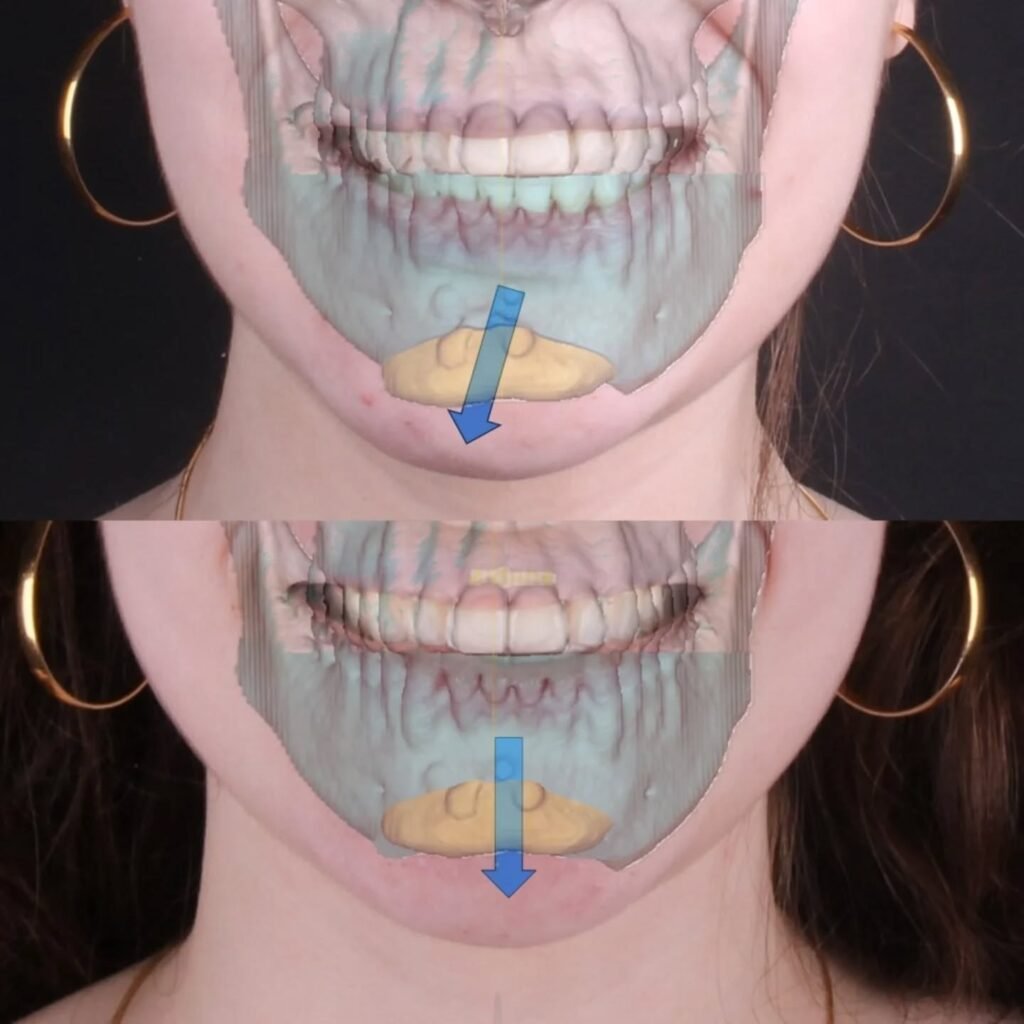

Cirurgia Ortognática

Você sente dificuldade para morder, falar ou até mesmo respirar corretamente? A Cirurgia Ortognática pode ser a solução! Esse procedimento corrige alterações ósseas no maxilar e mandíbula, melhorando a função mastigatória, a harmonia facial e a qualidade de vida.